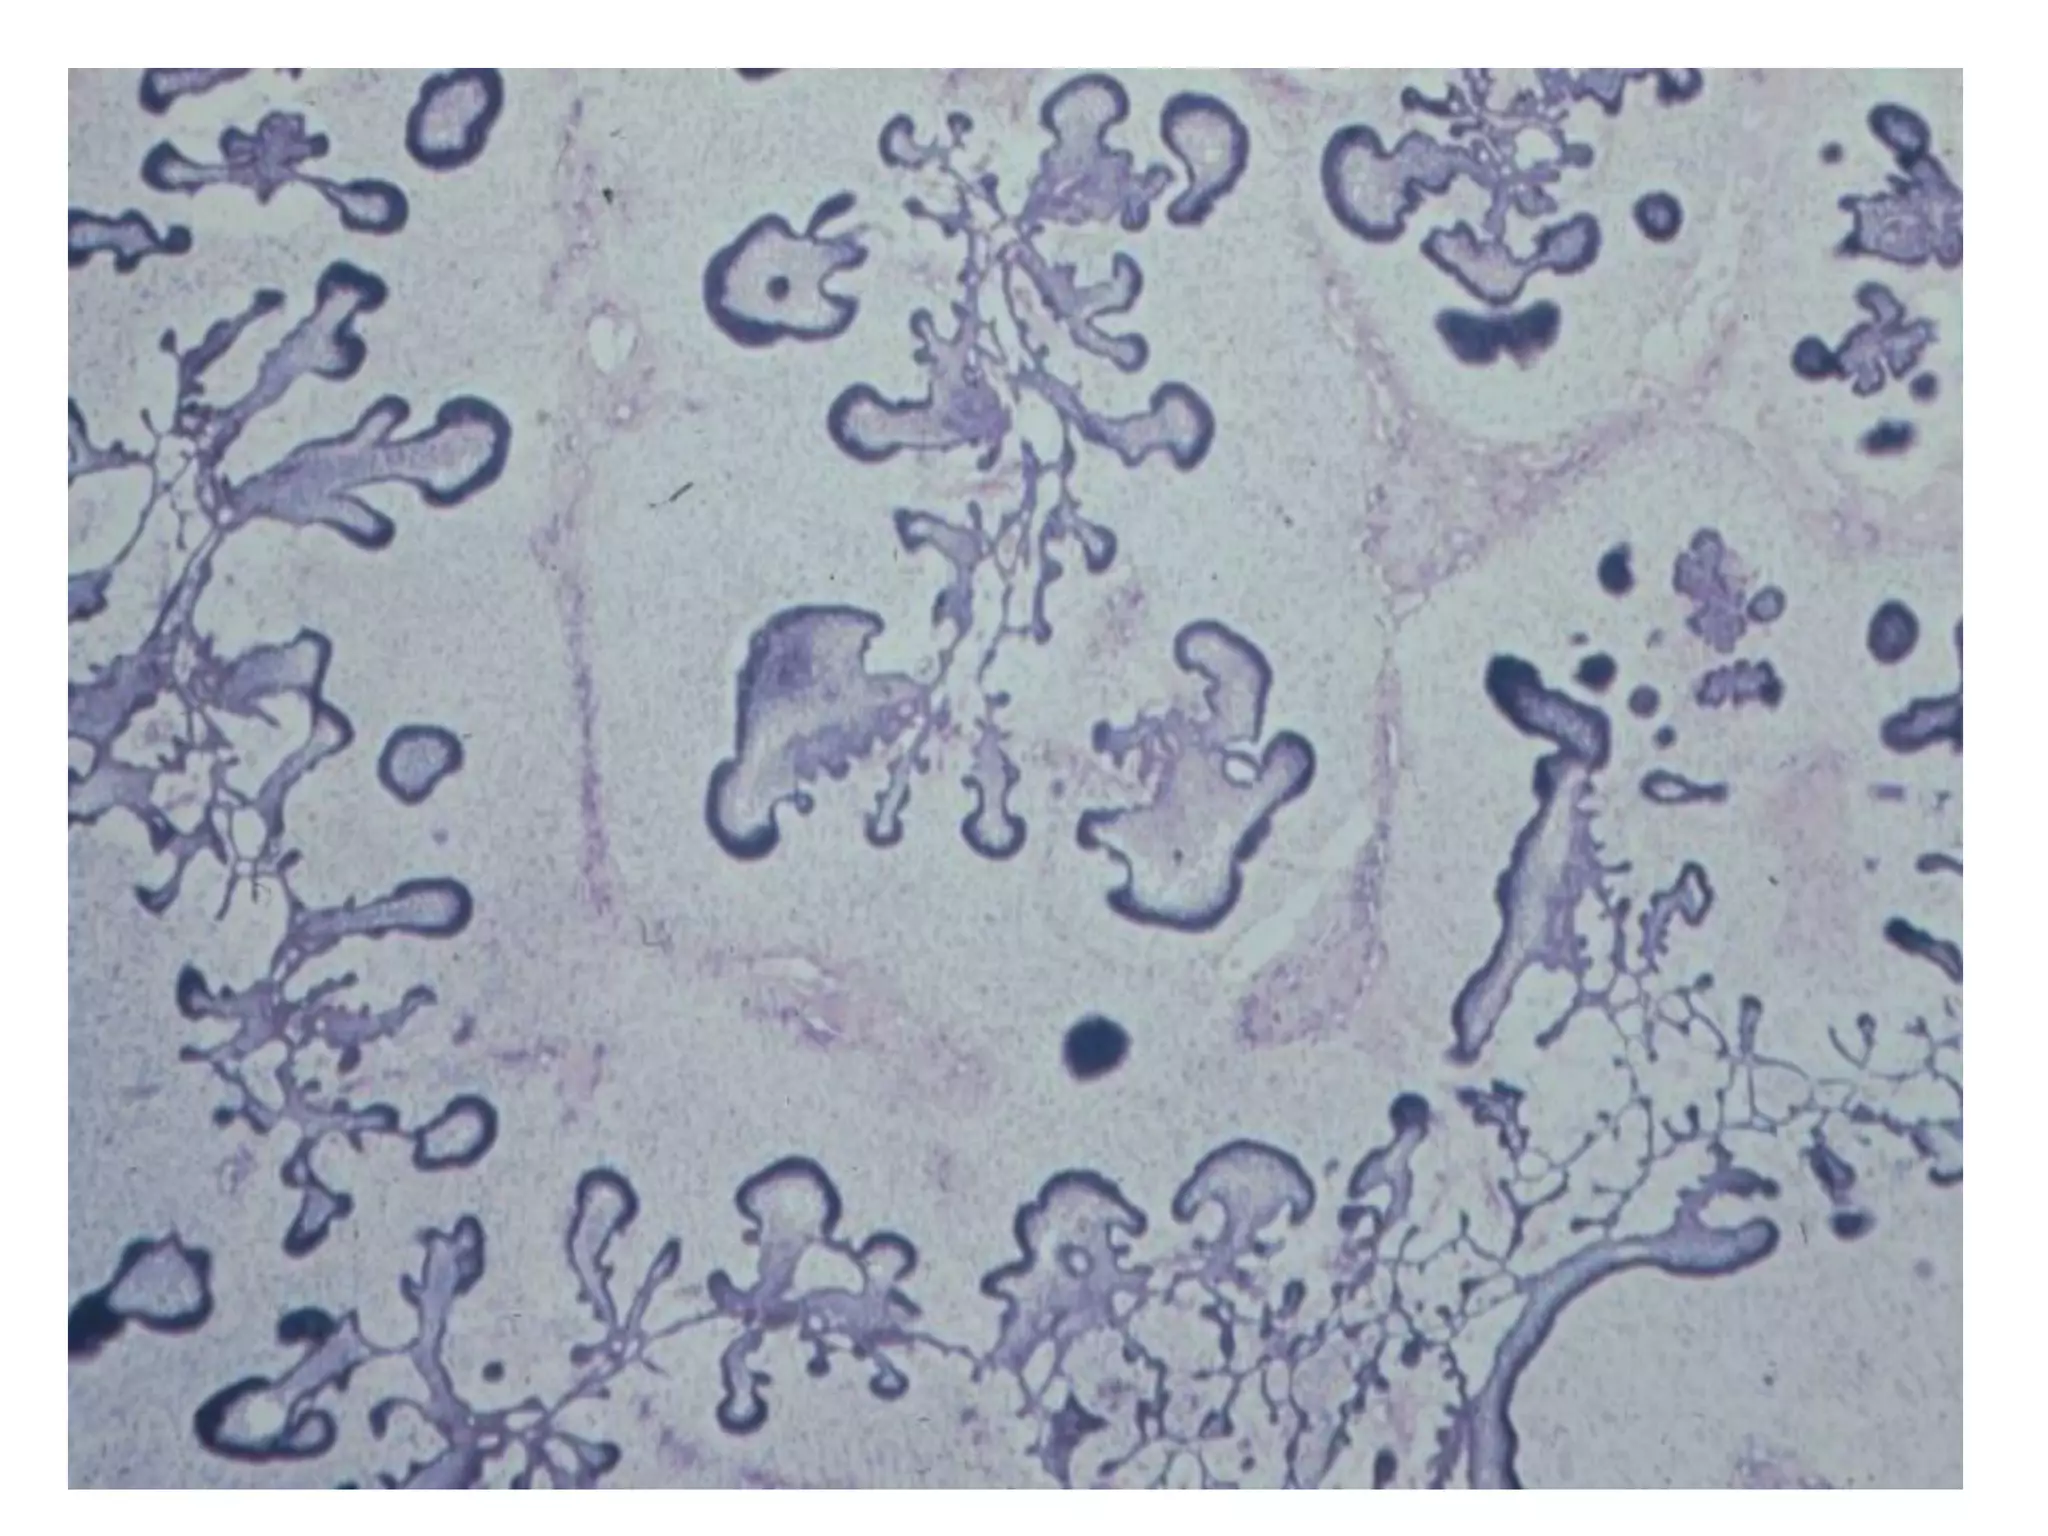

U nhaày do raêng

(Odontogenic Myxoma)

 Vò trí: baát cöù vò trí naøo cuûa 2 xöông haøm ,

XHD thöôøng gaëp hôn.

X quang: thaáu quang, nhieàu hoác. Ranh giôùi

khoâng roõ raøng.

Giaûi phaãu beänh:

 Goàm caùc teá baøo hình sao, hình thoi vaø hình

troøn naèm rôøi nhau trong moâ ñeäm nhaày loûng

leõo vôùi moät ít boù sôïi collagen.

 Caùc teá baøo bieåu moâ khoâng caàn thieát cho chaån

ñoaùn.

 Coù theå nhaàm vôùi u sôïi nhaày-suïn

(chondromyxoid fibroma) hoaëc vôùi bieán ñoåi

daïng nhaày trong bao raêng hoaëc nhuù raêng.